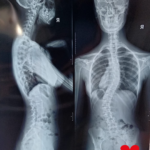

Erikai Maria Stingaciu este o adolescentă de 15 ani care se confruntă cu un diagnostic sever de scolioză dorsolombară progresivă, o afecțiune care îi modifică zilnic postura și îi afectează profund calitatea vieții.

A urmat zilnic ședințe de kinetoterapie, a purtat un corset rigid tip Cheneau timp de 23 de ore din 24 și a trecut prin multiple consultații și investigații în centre medicale din țară. În ciuda tuturor eforturilor, evoluția a continuat, iar în februarie 2026, în urma unui nou control, medicii au confirmat caracterul progresiv al scoliozei și necesitatea unei intervenții chirurgicale.

În prezent, Erika continuă să poarte corsetul zilnic și să urmeze terapii, însă acestea nu mai pot opri evoluția deformării coloanei. Singura soluție rămasă este intervenția chirurgicală, care îi poate reda șansa la o viață fără durere și fără limitările actuale.